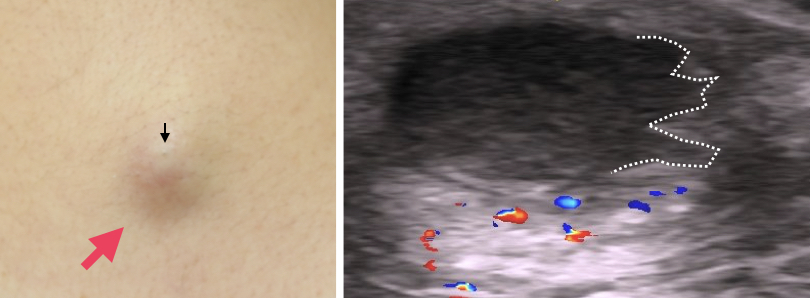

*粉瘤腫(アテローマ、epidermal cyst)とは?

その中で、表皮嚢腫(粉瘤、アテローマ)のくりぬき法を紹介します。皮膚外科特有の手技で、4mmの穴から倍以上の大きさのできものを取り出します。

局所麻酔後にトレパンで4mmの穴をあけます。何故か3mmではうまくいかないんです。

次に腫瘤をつまみ、一気に中身を押し出します。4mmの穴から、1cm以上のできもが排出されました。

取り残しがないか、肉眼的に十分に確認します。取り残しがあると再発しますからね。穴はこのままでも自然に閉じますが、このケースでは縫合した方がきれいですね。